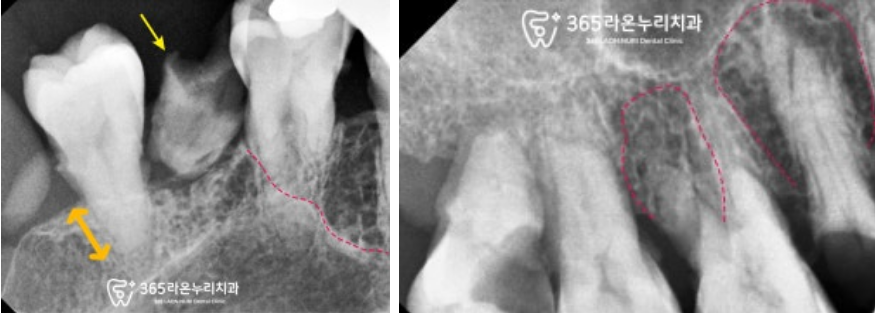

조금 더 세밀하게 진단하기 위하여

파노라마 엑스레이 촬영을 했는데요,

아래 양쪽 어금니는 모두 없으신 상태고

나머지 남아있는 자연치도

충치와 부러짐으로

수명을 다해보이는 이들이 많이 보입니다.

염증이 있는 곳을 자세히 관찰하기 위한

치근단 x-ray 촬영을 했습니다.

염증이 있거나 뼈가 흡수되어 녹은 곳은

방사선 투과성으로 나타나는데

생각보다 상태가 그리 좋지는 않습니다.

자연치를 잡아주는 주변 조직까지

회복하기 위해서는

전반적인 잇몸치료도 병행하여

오염된 곳을 청소해드려야겠습니다.

구치부도 어금니 뿌리를 뼈가 잘 잡아주지 못하고

전반적으로 염증이 있네요.